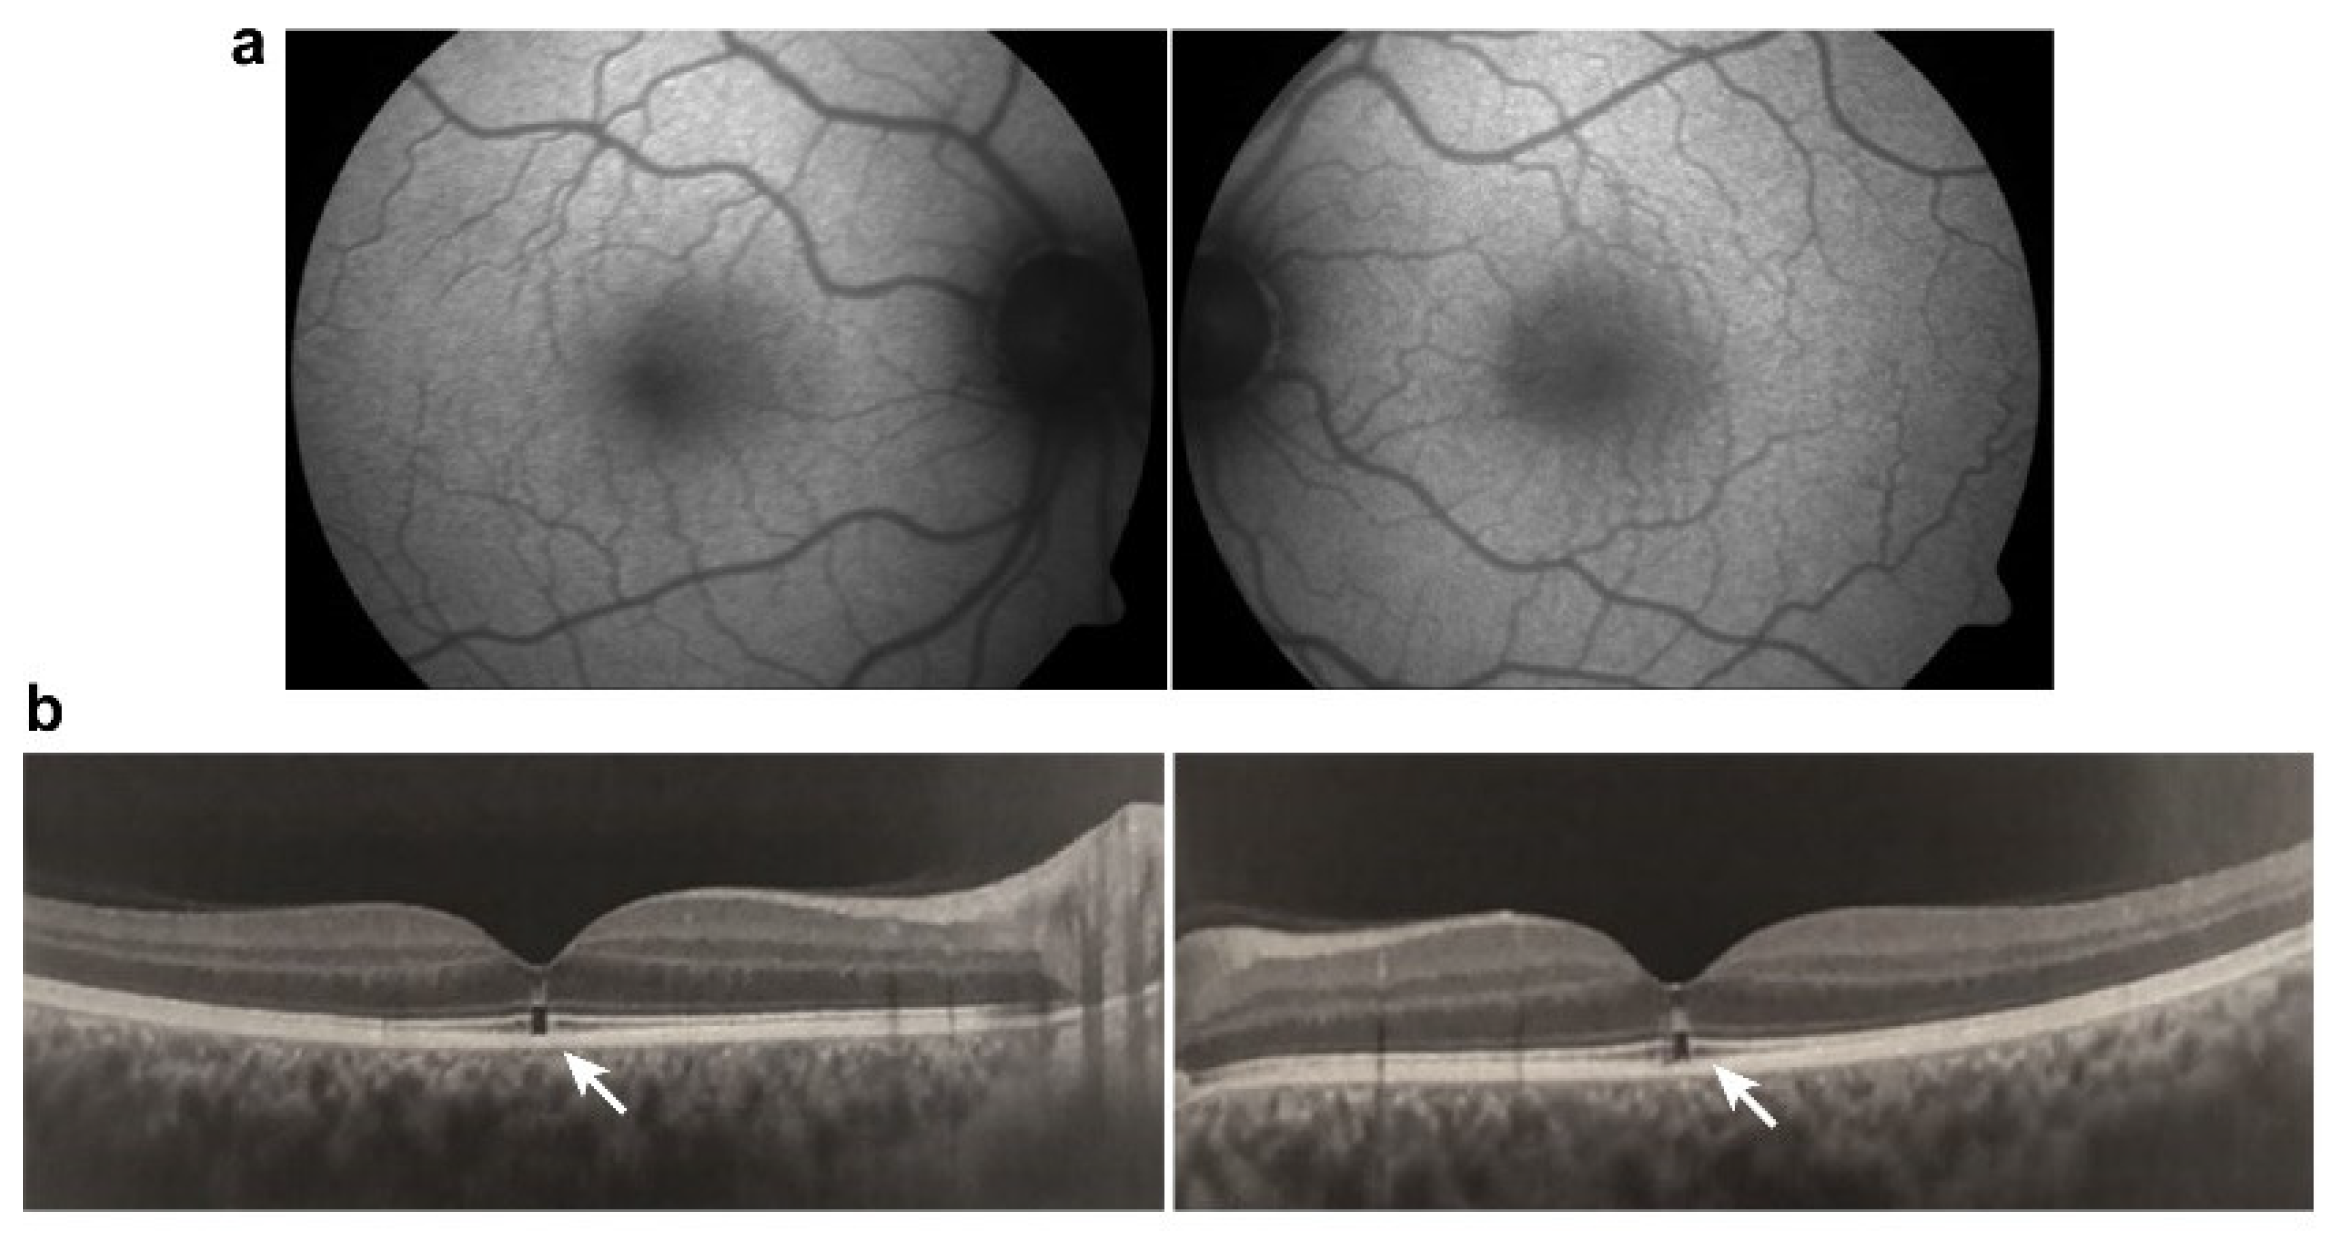

- Doshi, R.R.; Fortun, J.A.; Kim, B.T.; Dubovy, S.R.; Rosenfeld, P.J. Pseudocystic foveal cavitation in tamoxifen retinopathy. Am. J. Ophthalmol. 2014, 157, 1291–1298. [Google Scholar] [CrossRef]

- Wang, D.; Au, A.; Gunnemann, F.; Hilely, A.; Scharf, J.; Tran, K.; Sun, M.; Kim, J.H.; Sarraf, D. Pentosan-associated maculopathy: Prevalence, screening guidelines, and spectrum of findings based on prospective multimodal analysis. Can. J. Ophthalmol. 2020, 55, 116–125. [Google Scholar] [CrossRef]

- Hanif, A.M.; Armenti, S.T.; Taylor, S.C.; Shah, R.A.; Igelman, A.D.; Jayasundera, K.T.; Pennesi, M.E.; Khurana, R.N.; Foote, J.E.; O’Keefe, G.A.; et al. Phenotypic Spectrum of Pentosan Polysulfate Sodium-Associated Maculopathy: A Multicenter Study. JAMA Ophthalmol. 2019, 137, 1275–1282. [Google Scholar] [CrossRef]